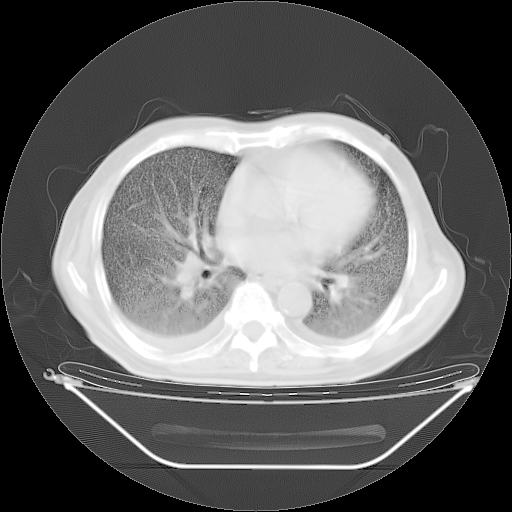

胸腹部CT,诊断意见:左上肺叶钙化灶、左侧胸膜局限性增厚并钙化、胆囊炎。描述部分肺组织呈磨玻璃样改变。